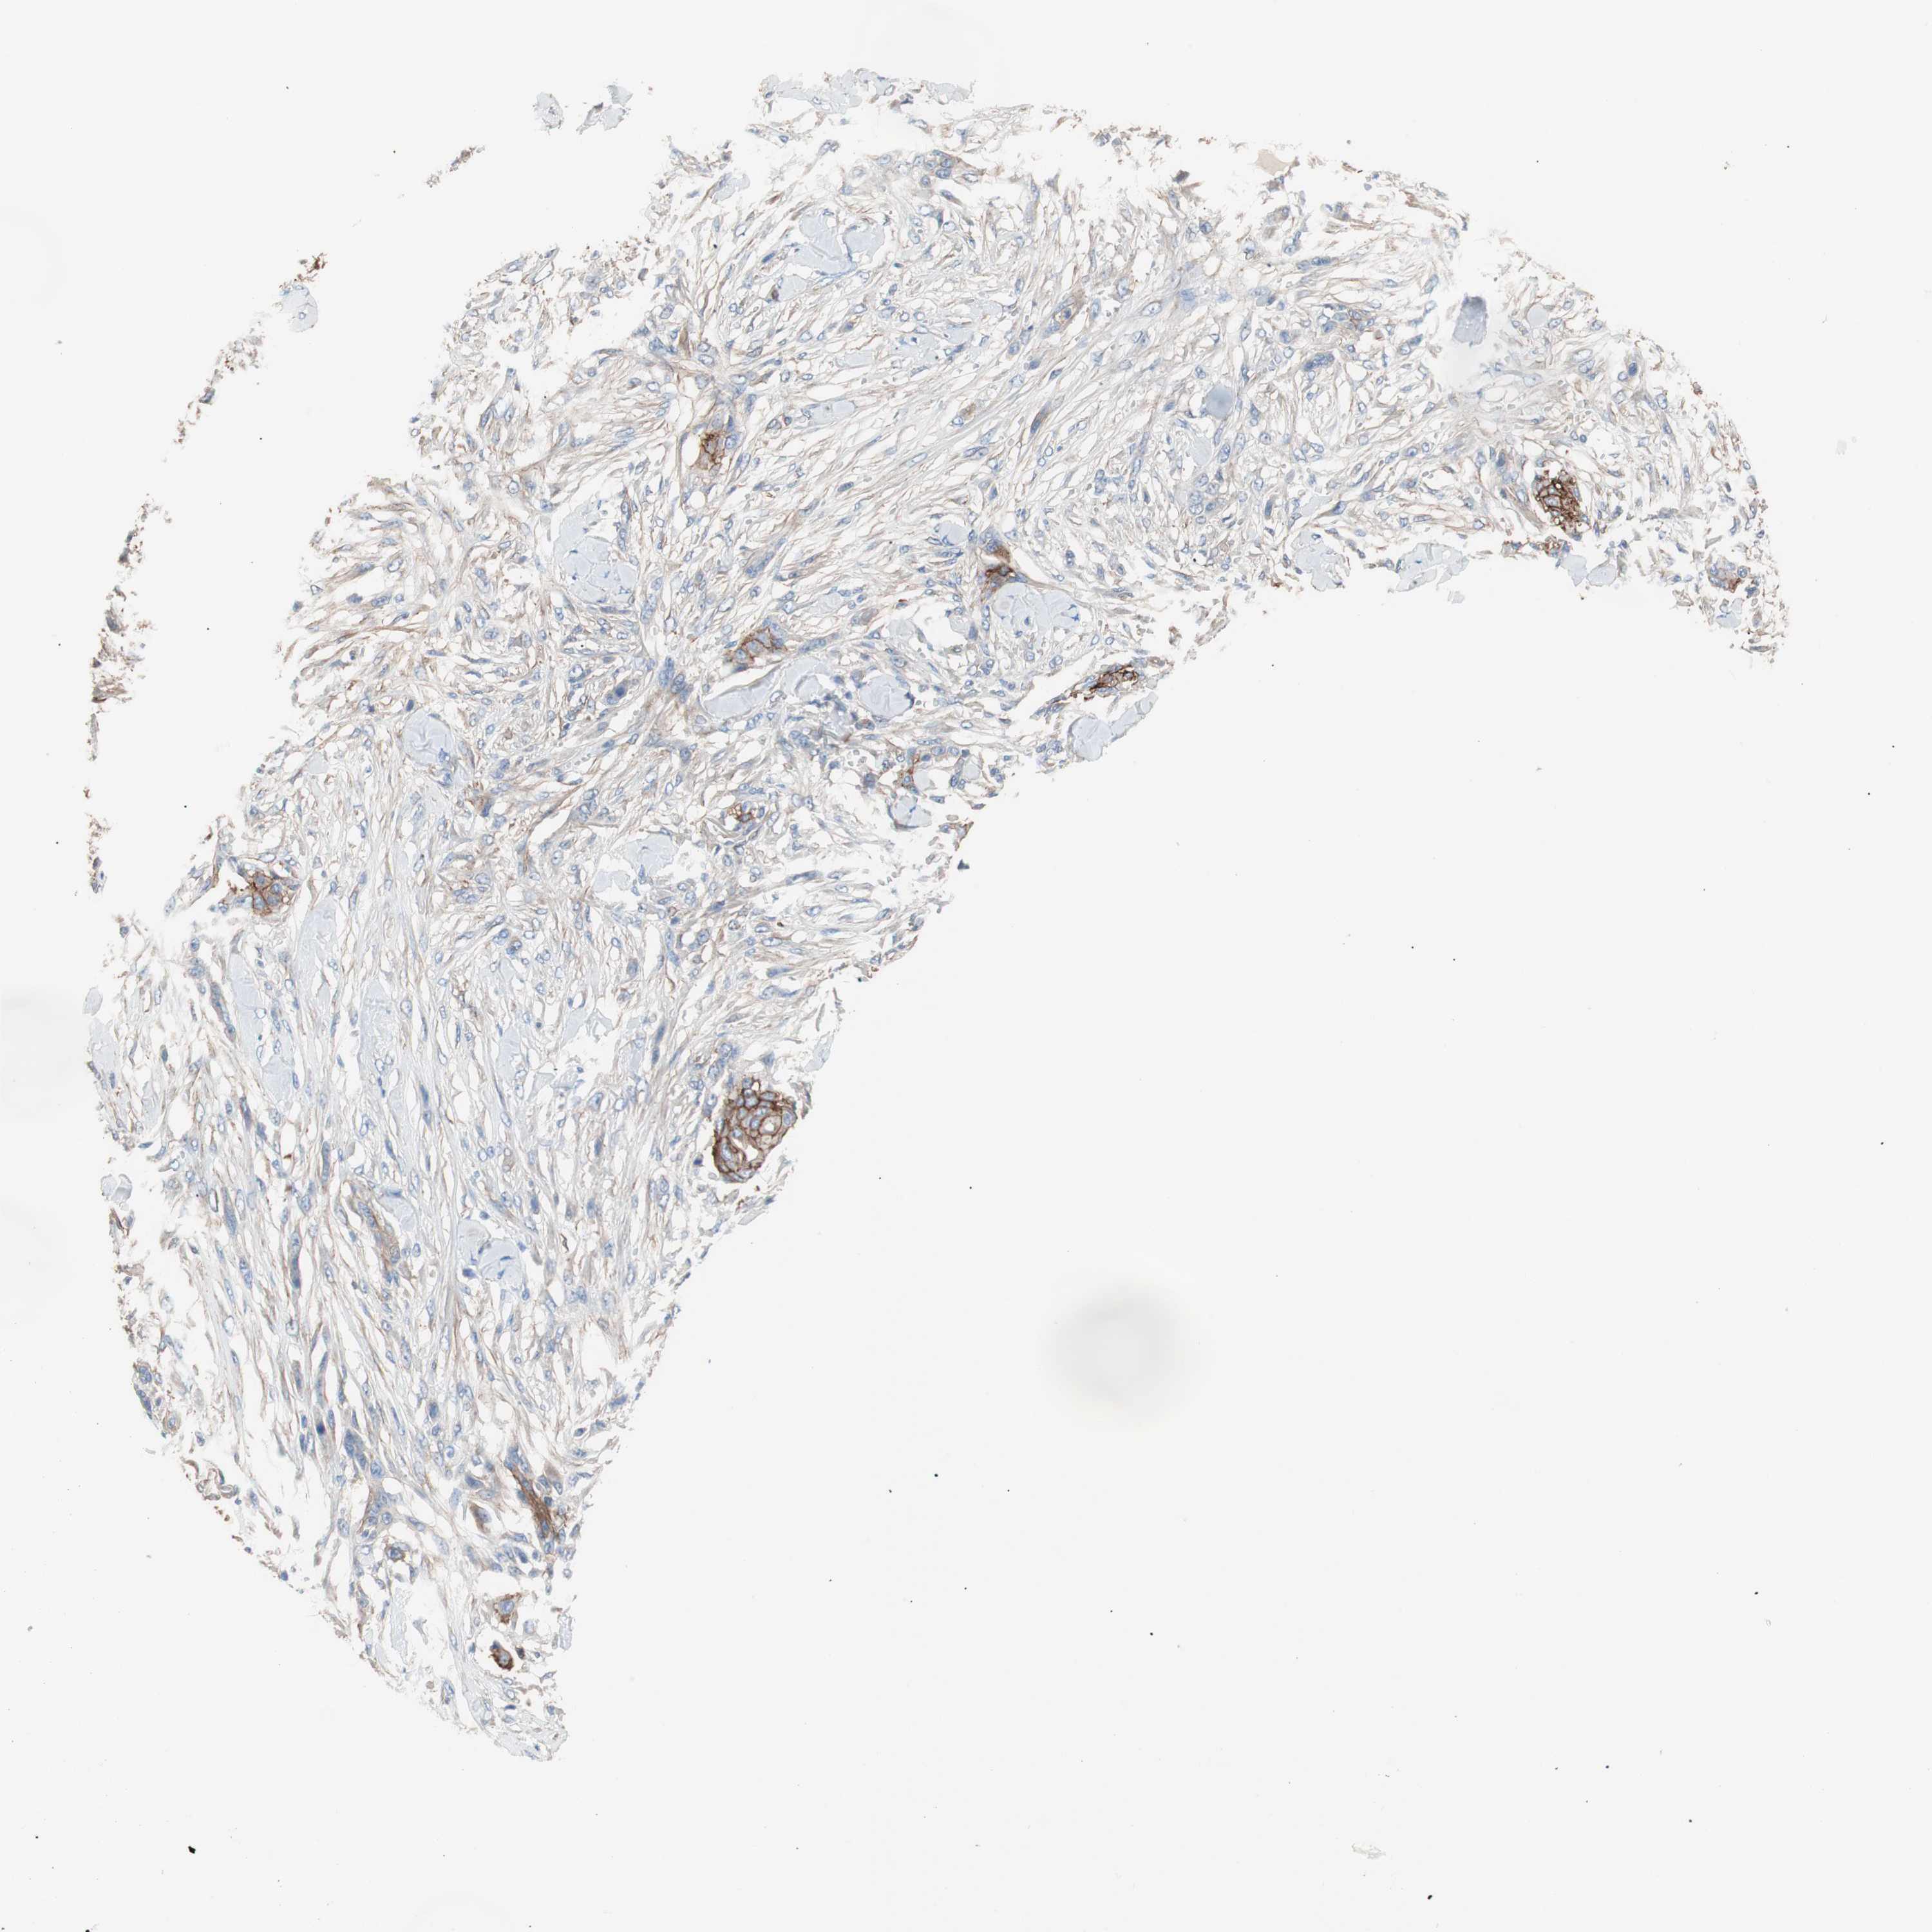

Antibody HPA006970

Staining

Not detected

Intensity

Negative

Quantity

None

Location

Basal cell carcinoma